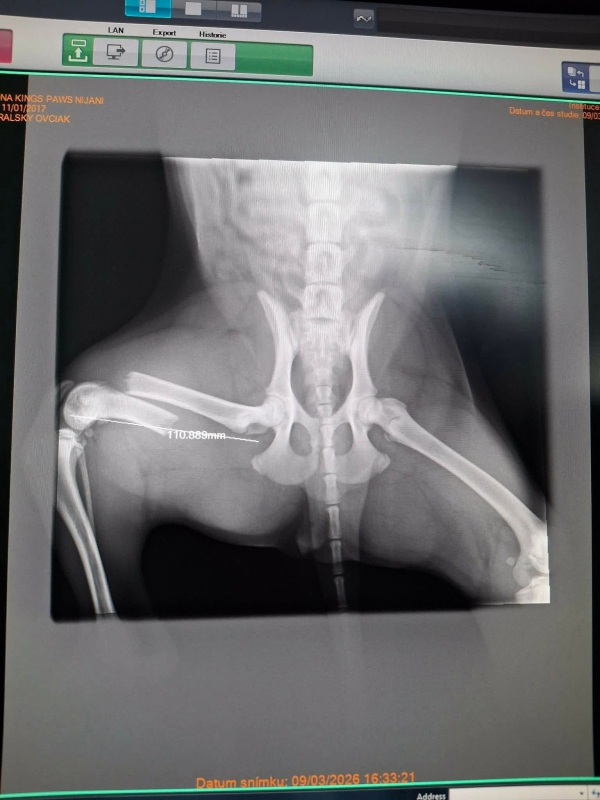

Včera sme prijali toto zranené šteniatko. Fenka zostala na pozorovanie na veterine a zistili že má zlomenú stehennú kosť :(

TERMÍN OPERÁCIE JE ZAJTRA 12:00 U PÁNA DOKTORA ADAMAŤA V TRENČÍNE

CENA OPERÁCIE 600€ :( :( :( Do zajtra musíme peniaze vyzbierať inak nebudeme mať z čoho zaplatiť ...